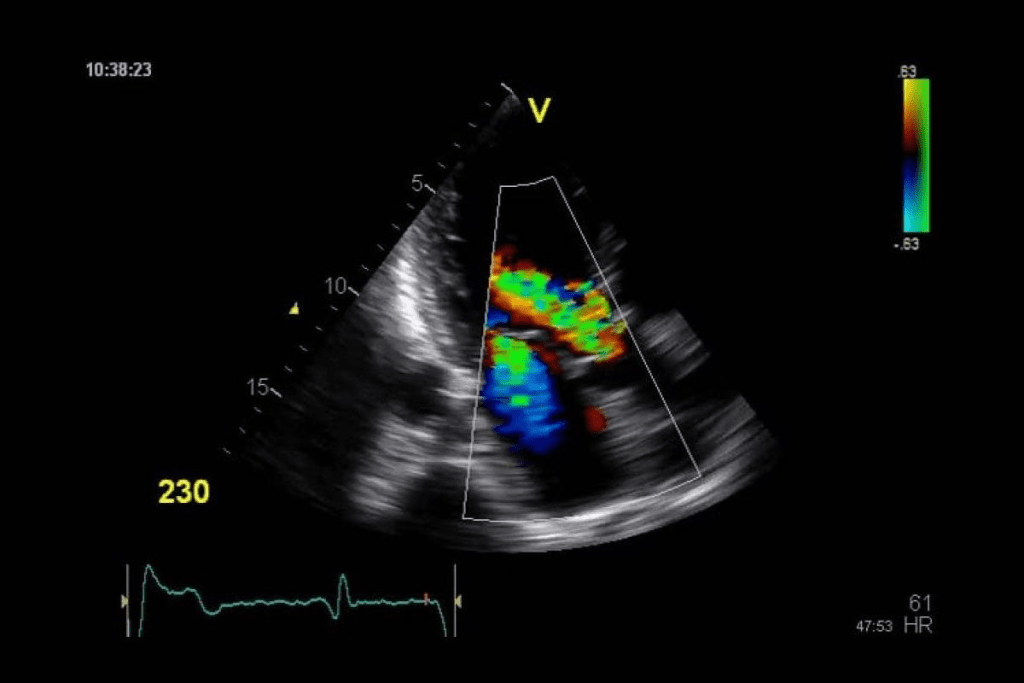

Color Doppler: What Red and Blue Actually Represent

Color Doppler adds blood flow info to the grayscale image. Red means blood is moving towards the transducer, and blue means it’s moving away. This helps doctors check blood vessel health and tumor blood supply.

The color’s brightness shows how fast the blood is moving. Brighter colors mean faster blood flow. This is useful for spotting problems like stenosis or vascular malformations.

Ultrasound imaging is key in finding cancer. It shows specific signs of bad tumors. Techniques like Color Doppler help tell good from bad tumors by looking at blood flow.

The Role of Blood Flow Patterns in Cancer Diagnosis

Blood flow patterns seen with Color Doppler ultrasound are vital in cancer diagnosis. Malignant tumors show increased vascularity and abnormal blood flow patterns. This shows their aggressive nature.

Using advanced ultrasound like Power Doppler helps see blood flow better. This helps tell if a tumor is benign or malignant.

Red and blue colors on ultrasound images show blood flow. They don’t directly mean cancer. Instead, they show the blood flow’s direction and speed in the body’s vessels.

Doppler ultrasound technology uses Doppler shift to check blood flow. Sound waves change frequency when they hit moving blood cells. This change is shown as colors on the ultrasound: red for flow towards the transducer, and blue for flow away.

Doppler flow signals help check vascular conditions. Doctors use these signals to find blood flow problems. This can help spot issues like cancer.

Tumor Vascularity and Blood Flow Patterns

Tumors grow and spread by getting a blood supply. Tumor vascularity is when new blood vessels form in a tumor. Doppler ultrasound can spot these vessels and check their blood flow.

Malignant tumors have special blood flow patterns. They have more blood vessels and irregular shapes. Doctors can learn about the tumor by looking at these patterns.

When Red and Blue Patterns May Indicate Malignancy

Red and blue on an ultrasound don’t always mean cancer. But, some Doppler flow signal traits can hint at cancer. For example, fast or chaotic blood flow in a tumor might suggest cancer.